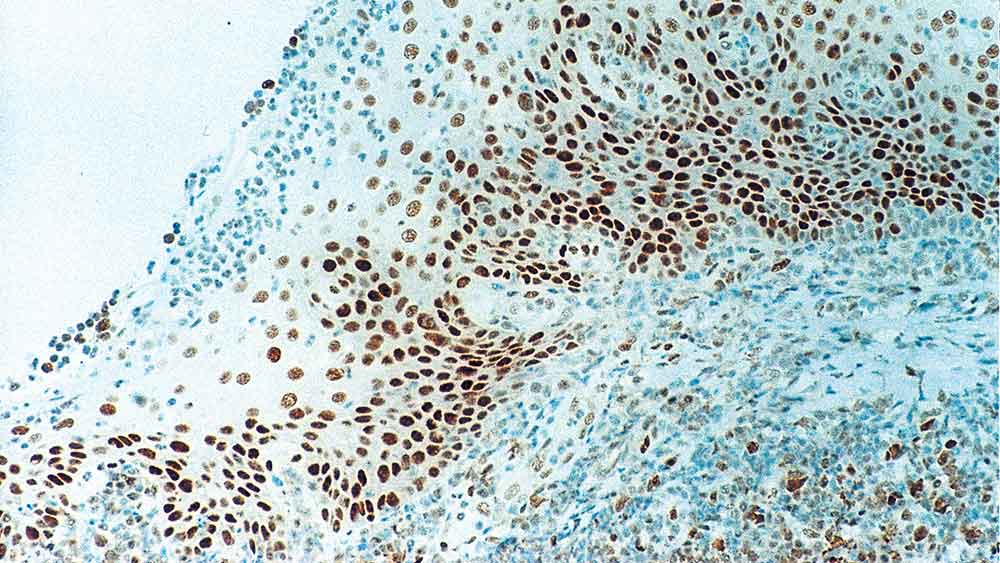

Retinoblastoma (Rb) is a rare tumor of the retina associated with mutations of chromosome 13. The nuclear phosphoprotein encoded by the Rb tumor suppressor gene is present in many cells and may indirectly regulate cell growth by activating the transcription factor ATF-2. Activation of ATF-2 initiates expression of TGF-beta2, which in turn inhibits transcription of genes affecting cell growth. Bilateral mutation of the Rb gene may potentially play a role in the development of a number of malignant tumors.

NCL-L-RB-358 was raised to the N-terminal region of the Rb gene protein.

Retinoblastoma Gene Protein is recommended for the detection of specific antigens of interest in normal and neoplastic tissues, as an adjunct to conventional histopathology using non-immunologic histochemical stains.